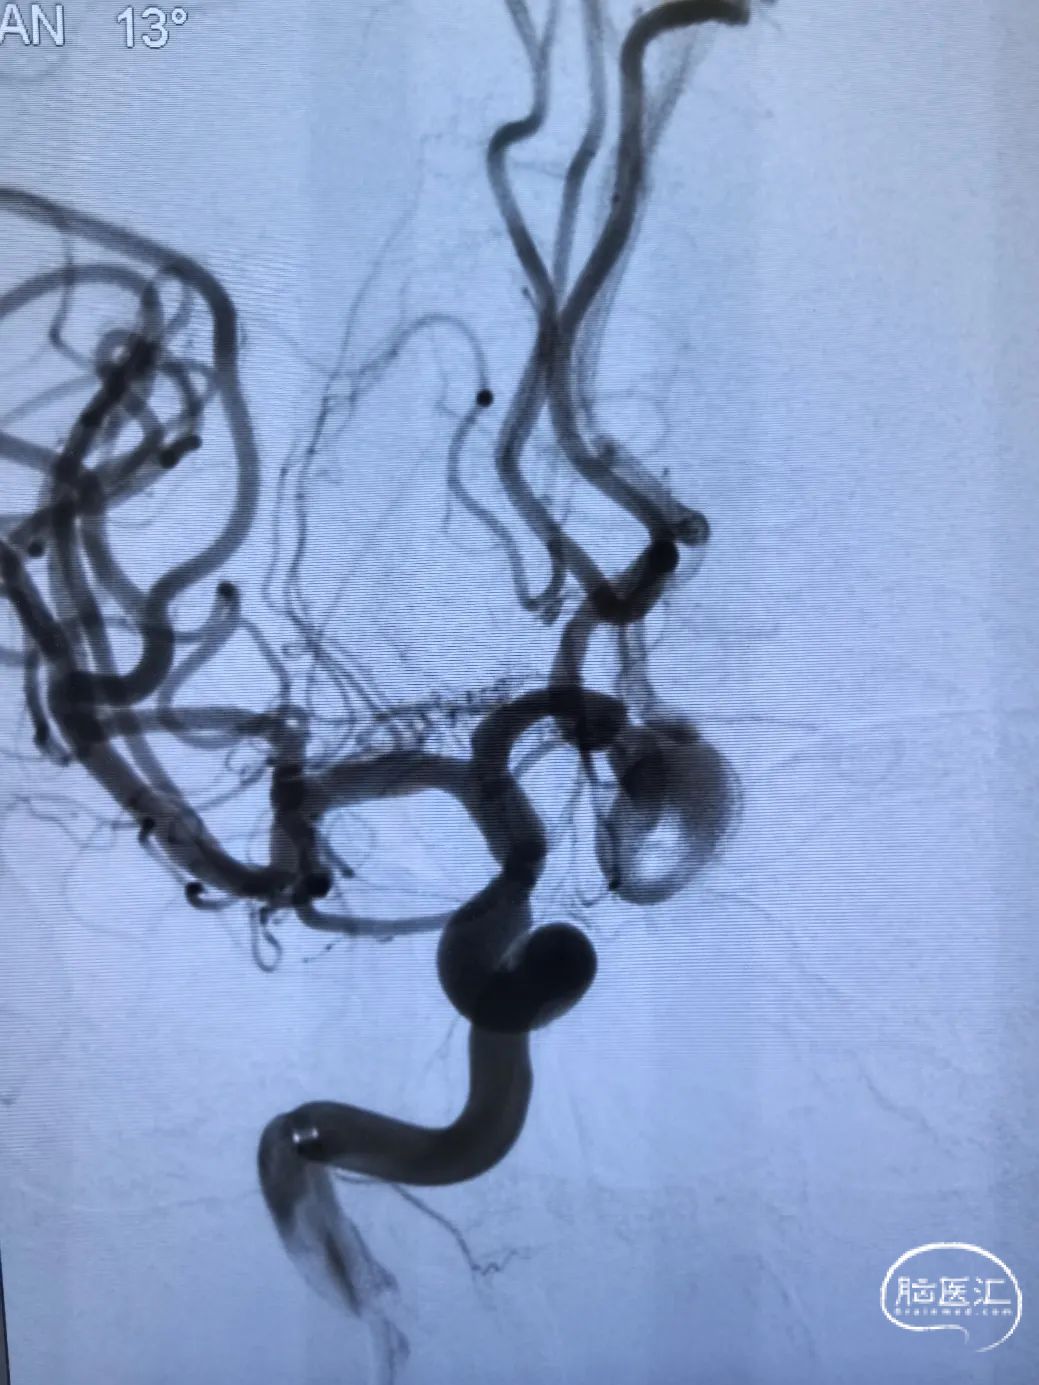

造影确认远端打开良好,定位后完全释放支架。

支架置入后造影显示,瘤内滞留明显,对侧造影几乎未见瘤内造影剂显影,手术结果满意。

1.该病例通过多方面考虑,选择密网支架植入术手术方案,且锚定区仅为右侧ACA,不影响对侧血流。

2.Surpass Evolve输送顺滑,跟踪性强,在输送支架过程中,XT-27微导管头端稳定。

3.Surpass Evolve打开顺利,打开即贴壁。尤其支架的远端打开顺利,减少了小血管中释放密网支架的操作,降低了术中并发症的风险。